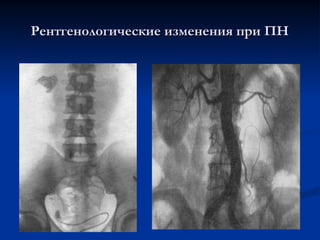

Рентгенологические изменения при ПН

 Р

Ранний

анний симптом -

симптом -

гипотония чашечек,

лоханок и мочеточника

на стороне поражения,

огрубение рисунка

сосочков.

 На

На поздних стадиях

поздних стадиях -

-

деформация чашечно-

лоханочных систем,

уменьшение толщины

почечной паренхимы,

размеров пораженной

почки или ее отдельных

сегментов.